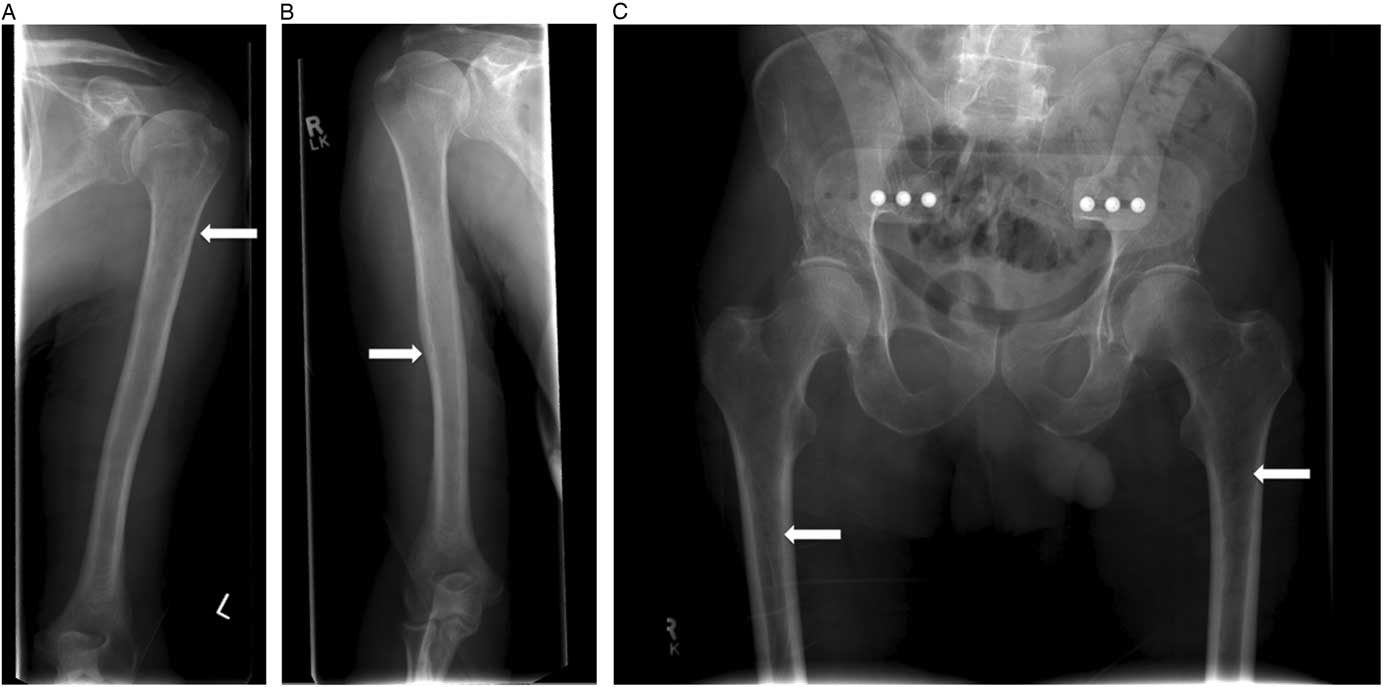

This patient was admitted and received further investigations to elucidate the cause of his compression fractures, pancytopenia, and hypercalcemia. The serum protein electrophoresis revealed an elevated gamma globulin, and urine protein electrophoresis revealed free lambda light chains. Immunoglobulin A (IgA) was significantly elevated at 39.36 (range 0.60–4.20) mg/L, as was the β2 microglobulin level at 4.80 (range 1.00–2.60) mg/L. A bone marrow biopsy confirmed a diagnosis of multiple myeloma. A skeletal survey demonstrated additional lucencies in the proximal femur and humerus bones bilaterally (Figure 3, A–C). The patient was followed by the hematology service for further management.

Figure 3 A, B) Skeletal survey identified radiographic lucencies in the proximal humeri and C) femurs bilaterally.